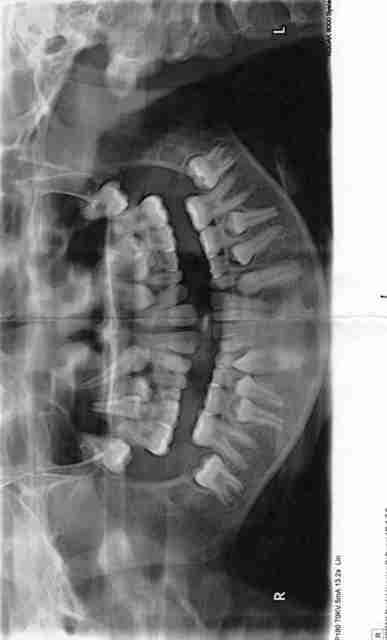

Au vu de la pano quel âge a ma petite patiente??

Au vu de la pano, moi je dirais environ 9 ans ??

Elle est sans doute plus âgée, car les apex des canines et prémolaires sont quasiment fermés.

Dent surnuméraire à l'apex de 11.

Gros retard d'eruption.

Apex de 35 et 45 fermés.

Apex de 13 et 23 fermés.

Sujet agé de 12 ans (+ ou - 12 mois)

Sinon, si il y a qqch qui me gêne : les dents sont quasiment voir totallement formées mais ne sont pas sur l'arcade

de retour de Barcelone, je vous donne la réponse elle a 12 ans et demi et effectivement il y a un petit problème, pas de résorption des dts de lait

La cause: inconnue mais j'ai juste trouvé un très fort déséquilibre alimentaire depuis toute petite, pourquoi pas??

si tu laisses faire mother nature la résorption étant à zéro pour les molaires entre autre ,les dts de lait seront encore là à 30 ans et surtout je crains une superbe ankylose des définitives, les canines sont déjà très hautes!

Pour l'action j'ai effectivement proposé à la patiente les extractions avec un suivi en parallèle ortho car en plus(cela ne se voit pas très bien)la 24 et la 25 se sont croisées à cause du blocage . Je pense qu'il est mieux de tout débloquer rapidement ds ce cas là.